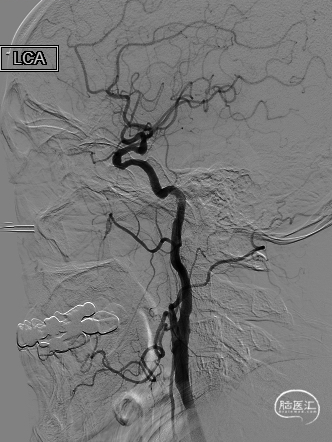

➢ 二期支架置入术

长SIM与6F导引导管同轴,泥鳅导丝引导下将6F导引导管送至颈总动脉远端(左图),保护伞到位(右图)。

4.0*30mm通桥白驹®球囊以6atm扩张(左图箭头),扩张完毕后多角度造影显示狭窄交前明显改善(中图箭头处),扩张完毕后支架置入(右图箭头处)。

术后常规复查头CT未见明显出血。